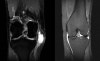

MRI : 거위발점액낭염(pes anserinus bursitis)

간혹 점액낭 주위에 뼈가 툭 튀어나온 사람도 있습니다. 생각보다 흔한 소견이며 그렇게 뼈가 튀어 나와 있어도 통증이 없는 사람도 많습니다(증상이 없다면 치료의 대상이 아닙니다).